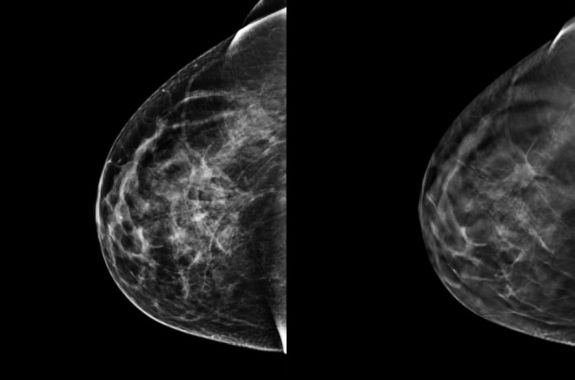

3-D Mammography Detects More Cancers, But Will It Save Lives?

A new study suggests that 3-D mammography detects more cancers than traditional digital mammography. But the technology is expensive, and there’s no indication yet that it catches more dangerous cancers, or is saving more lives.